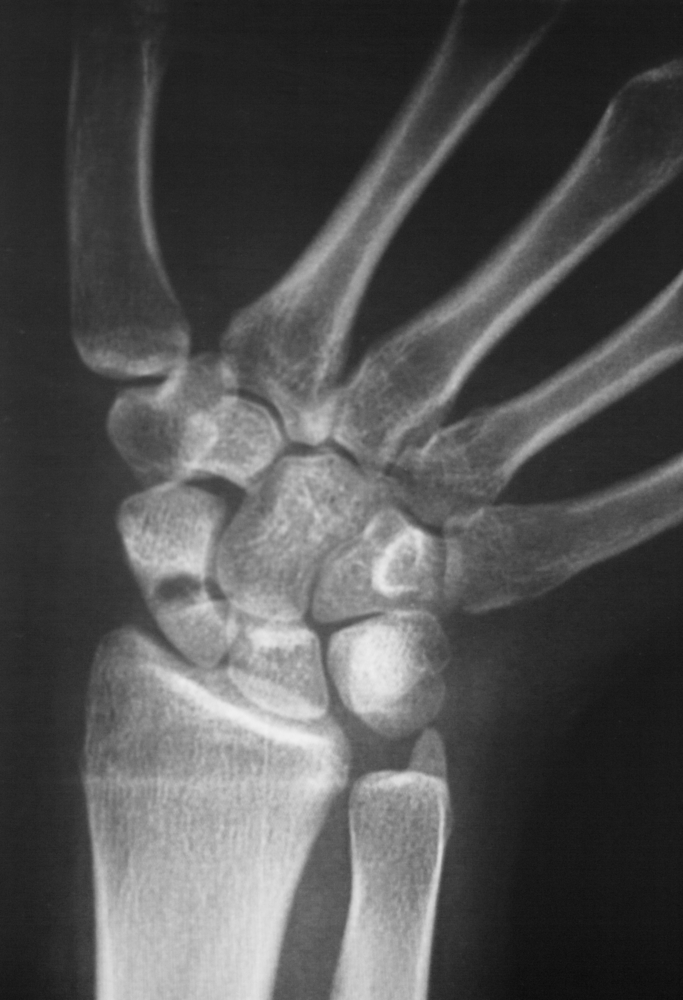

Dilbio srityje yra dvi pagrindinės kaulo struktūros – stipinkaulis ir alkūnkaulis. Alkūnkaulis prasideda ties riešo išorine dalimi, o stipinkaulis – vidine. Ties alkūnkaulio galu, prie pat plaštakos, susiformavęs kaulinis išsikišimas, vadinamas alkūnkaulio pentine atauga. Ji įsitvirtina riešo sąnario kremzlėje ir užtikrina riešo tvirtumą bei lankstumą. Kai šioje vietoje įvyksta lūžis, jis vadinamas alkūnkaulio pentinės ataugos lūžiu.

Dažniausias alkūnkaulio pentinės ataugos lūžio požymis – staigus skausmas. Paprastai šis lūžis būna kartu su stipinkaulio lūžiu, todėl neretai jaučiamas skausmas ne šalia alkūnkaulio ataugos, o arčiau stipinkaulio – riešo vidinėje pusėje.

Alkūnkaulio pentinės ataugos lūžiai dažniausiai įvyksta, kai krentant bandoma atsiremti ištiesta ranka. Tai labiausiai paplitęs riešo bei rankos kaulų lūžių priežastis.

Lūžusius kaulus būtina tinkamai sugrąžinti į pradinę padėtį ir užfiksuoti, kad jie galėtų suaugti. Priklausomai nuo lūžio sudėtingumo, taikomi skirtingi gydymo būdai.

Nesmarkiam lūžiui paprastai pakanka riešo imobilizacijos – riešas sutvirtinamas specialiu gipsu ar įtvaru. Kartais prieš tai kaulai sulygiuojami, vadinama kaulų repozicija, kuri kai kuriais atvejais atliekama be pjūvio.

Jei lūžis sudėtingas ar pažeisti kiti šalia esantys kaulai, dažnai reikalinga chirurginė operacija. Šiuo atveju gydytojas padaro pjūvį, sugretina kaulus ir naudoja metalinius varžtus ar kaiščius, kad fragmentai tinkamai sugijtų. Po operacijos dedamas tvirtas gipsinis arba stiklo pluošto įtvaras.